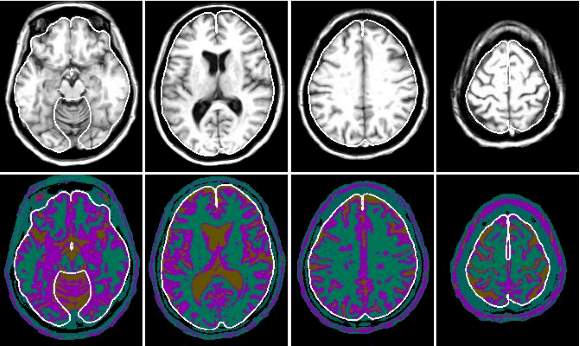

atrofija mozga